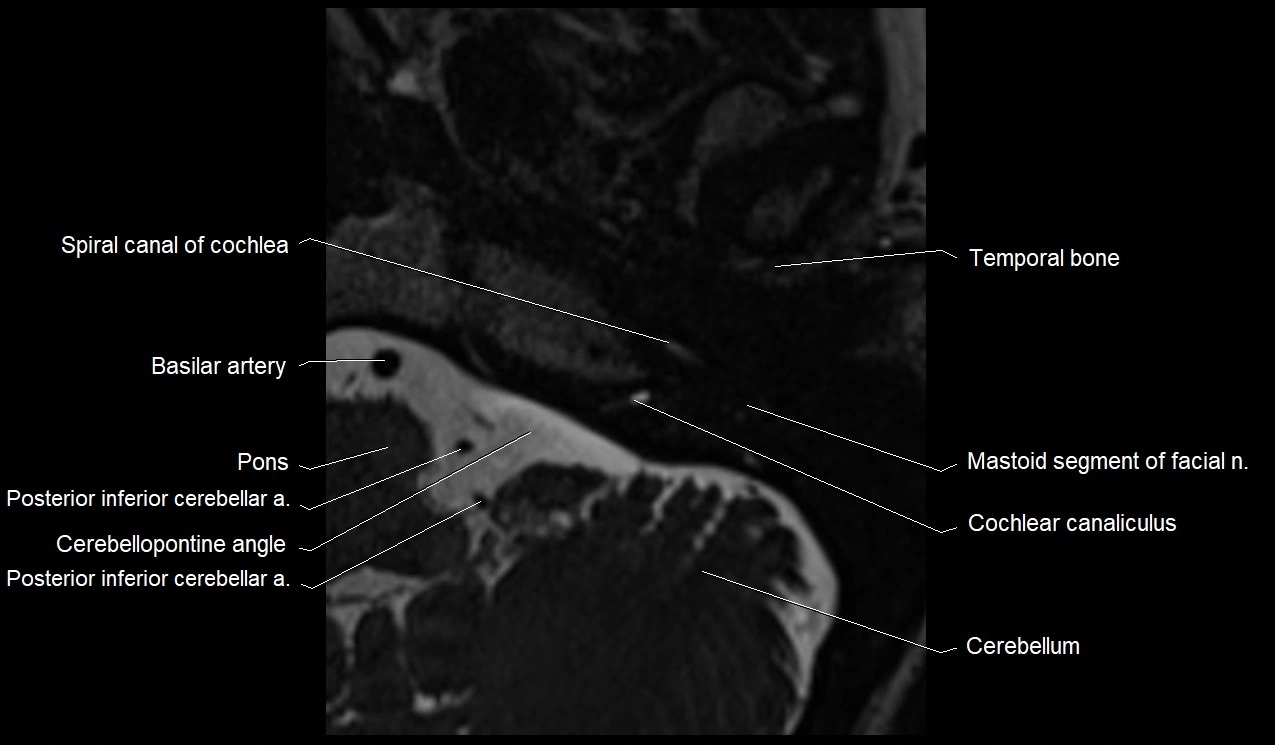

MRI images

image